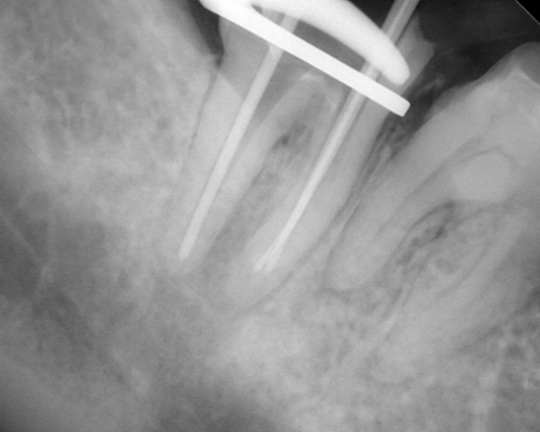

自費根管治療症例5 治療前(抜髄)

「奥歯ひどくしみて痛い。」(18歳女性)

前回の治療の時にすでにむし歯が深かったようです

悪いところを全て除去した結果、神経が露出していました、根管治療が必要です

レントゲン写真

ラバーダムシートを固定する金具が写っています、シートはバイ菌が

入らないように撮影時にも外しません

充填物がきちっとできるように何度も確認します

見た目よりもいかに無菌的に行えたかが大切です、見た目もきちっとできました